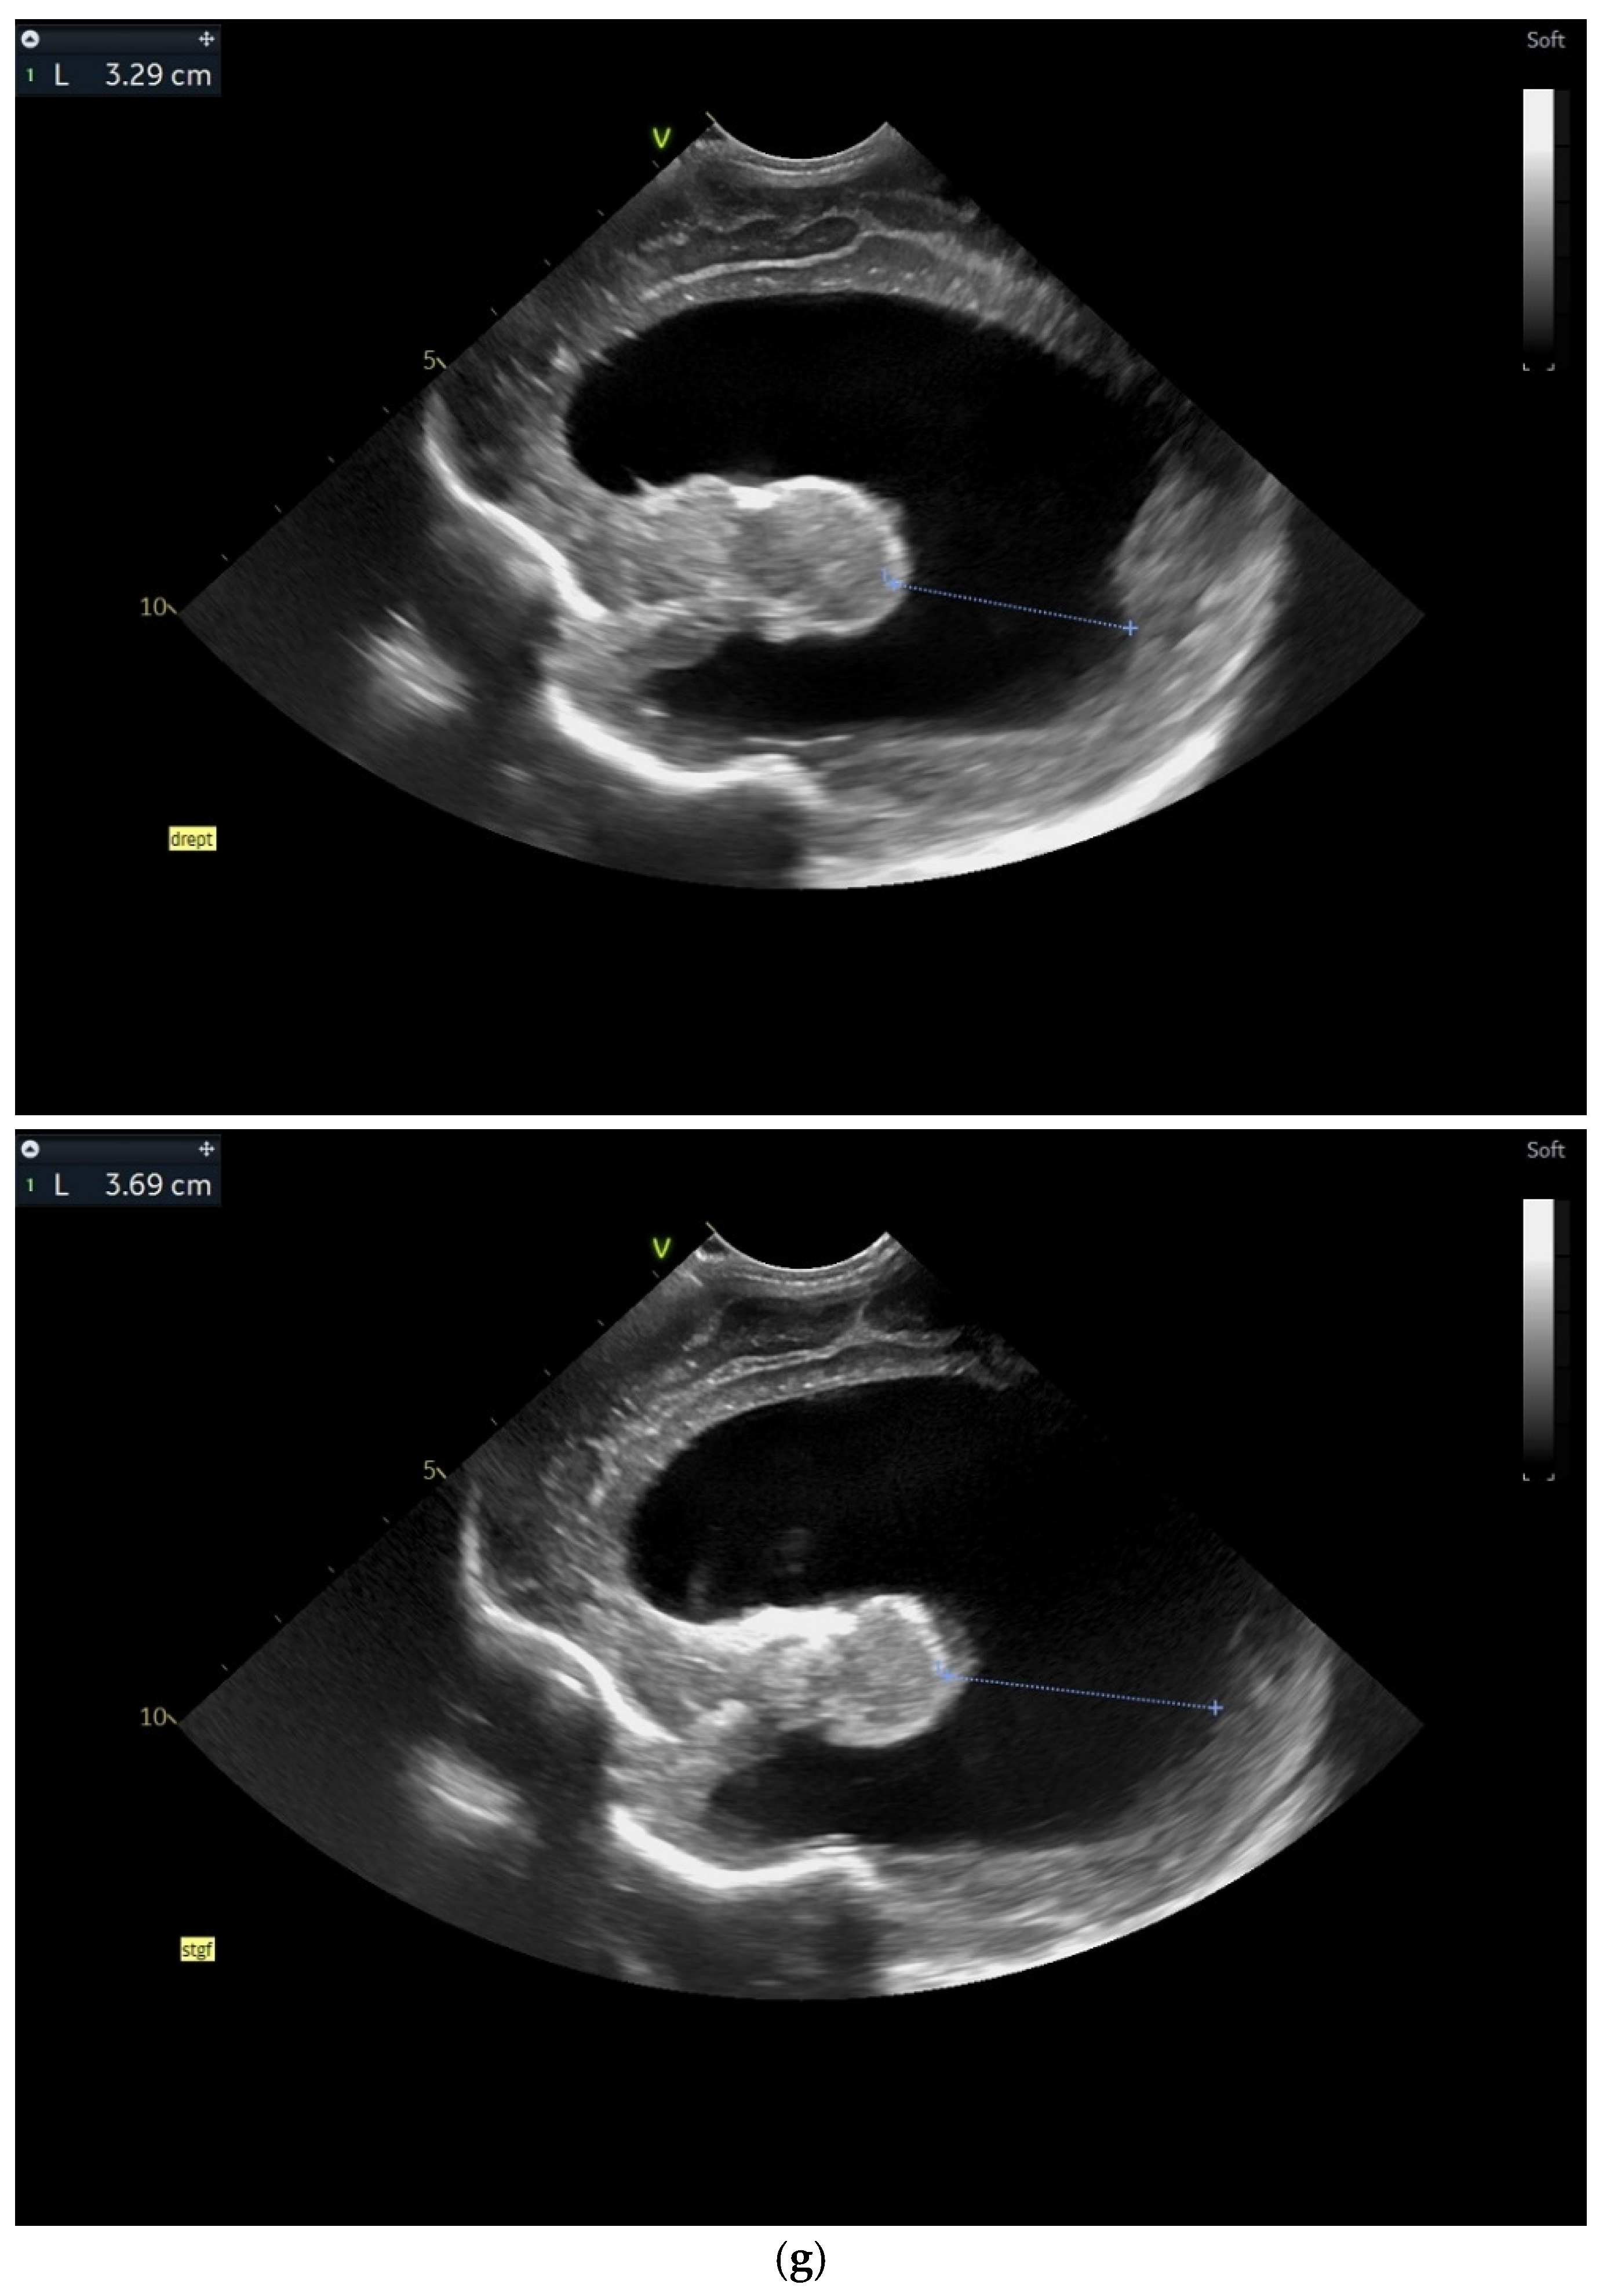

Figure 5.

(a,b) MRI—T2 sequence. Sagittal view. Antenatal. Yellow arrows indicate the place of the suspected tumor (personal image collection). (c) Cranial ultrasound. Sagittal view. Up—enlarged left ventricle. D1—thamalo-occipital distance. Down—enlarged right ventricle. D1—thalamo-occipital distance (personal image collection). (d) Cranial ultrasound. Sagittal view. Enlarged third ventricle. Fourth ventricle is normal. D1, D2—measurements of the third ventricle (personal image collection). (e) Cranial ultrasound. Transtemporal view. Enlarged third ventricle. Sylvian aqueduct is not visible. D1—measurement of third ventricle. LV AH—lateral ventricle anterior horn. LV OH—lateral ventricle occipital horn. V 3—third ventricle (personal image collection).

After stabilization, the cranial ultrasound exam revealed enlargement of the lateral ventricles and third ventricle, with a normal fourth ventricle. There was no visualization of the Sylvian aqueduct, which raised the suspicion of aqueduct atresia or stenosis (Figure 5c–e). There was no improvement seen in the cranial ultrasound examinations that followed.